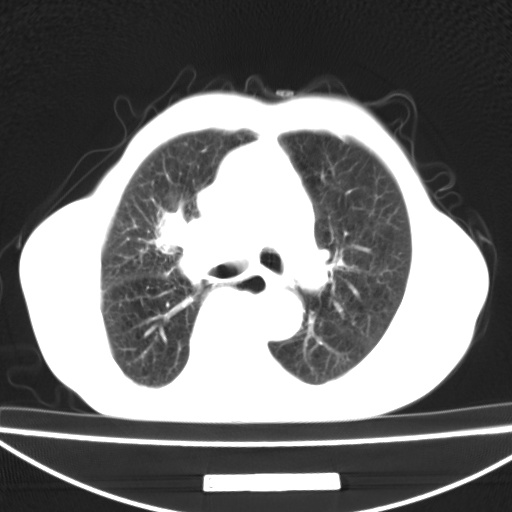

标题: CT13796:请会诊右上费病变!

患者男80岁,反复咳嗽多年,咳喘伴咯血1月

右上肺周围型肺癌伴肺门淋巴结转移.右上肺继发型肺结核.

右上肺周围型肺癌伴肺门淋巴结转移

右肺上叶占位性病变,考虑周围型肺癌,肺门淋巴结转移。要是能提供更多的临床资料就好了,以供鉴别诊断。

右肺尖周围型肺癌伴肺门淋巴结肿大

右肺尖结核

右肺上叶占位性病变,考虑周围型肺癌,肺门淋巴结转移。

右上肺周围型肺癌伴肺门、纵膈淋巴结转移

考虑为:右肺上叶肺癌伴阻塞性肺炎、右肺门及纵膈淋巴结转移。

右上肺结核合并右上肺癌,肺门淋巴结肿大